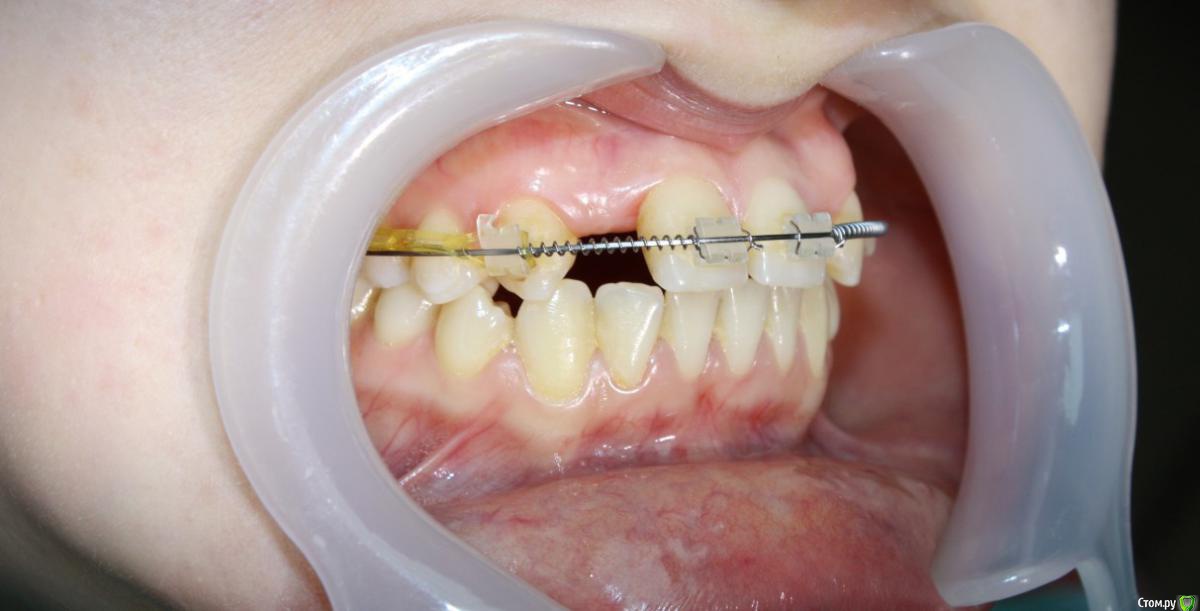

Здравствуйте коллеги! На консультацию обратилась пациентка, сейчас находится на ортодонтическом лечении. Предистория: три года назад обратилась к стоматологам с жалобой на неудовлетворительную эстетику фронтального отдела, вследствие врожденного отсутствия латеральных резцов. Ей было предложено ортодонтически создать место для боковых резцов, затем провести имплантацию и протезирование на имплантатах 12, 22.

Затем, с ее слов, идет длительный этап ортодонтии, почти 3 года, вследствие которого получили немного места для двоек, которого не достаточно для иплантации, так же центральные резцы ушли вперед, образовалась саггитальная щель.

Ортодонт предлагает удалять восьмерки, ставить брекеты Дэймон на вч и нч, мини винты в ретро молярную область  и продолжать ортодонтическое лечение, создавать место для двоек. Пациентка пока пошла делать новое КТ,

восмерки удалить надо было до.я сто раз не ортодонт ,но даймонд тут не нужен ,место тут создать очень даже можно ,при правильной тактике ортодонта.лечение только на одной челюсти? потеря опоры(получили разворот зубов), убрать разворот вот и появится немного еще место,корни (наклон) единицы и клыка в удачном положении,я за нормальную ортодонтию

2. доклеить брекеты на семерки , переклеить 6-ки, таким образом  устранить ротацию шестерок  и усилить опору в боковом отделе.

3. доклеить отсутствующие брекеты, создать нормальную форму зубного ряда

4. сагитальная щель здесь небольшая (если учесть тот факт, что протрузию уберем ,  и тем более, если поставим брекеты на Н Ч ,  за счет устранения скученности)